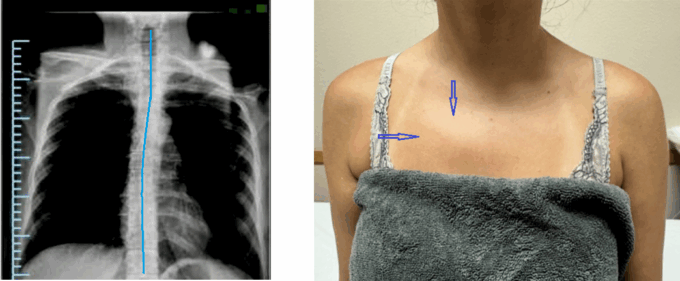

Please compare the right and left parasternal areas, paying particular attention to the right side of her upper chest. There is a visual bulge in her right parasternal region (indicated by blue arrows in the photo).

Thus, the patient’s anterior chest suggests the possible presence of an early stage of Scoliosis with thoracic curvature directed to the right.

The patient suggested visiting her family doctor, who referred her for an X-ray. Radiologist confirmed the 1st-stage of thoracic curvature (indicated by the blue line on the X-ray).

The presence of visual differences in the parasternal areas is due to the upper ribs’ anterior displacement caused by the rotation of the bodies of the upper thoracic vertebrae. In this scenario, it is useless to treat her middle back pain in the form of different syndromes of muscle dysfunctions since the upper thoracic curvature must be decompressed first.